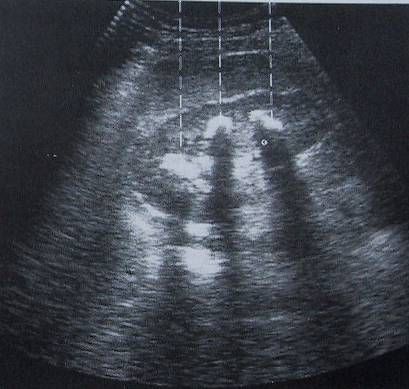

Sonographie |

(Ultraschalluntersuchungen) |

Ultraschalluntersuchungen (Sonographie) ermöglicht die Untersuchung von Organen im Bauchraum (Leber, Gallenblase, Nieren,Bauchschlagader), des Herzens und der Schilddrüse sowie der Halsschlagader. Hierbei können Veränderungen der Organe harmloser(z.B. Cysten) aber auch gefährlicher(z.B. Bauchaortenaneurysma) Art festgestellt werden. Ebenfalls kann hierbei sehr sicher beurteilt werden, ob zum Beispiel Gallensteine oder Nierensteine vorhanden sind. Es handelt sich um ein harmloses und für den Patienten nicht belastendes Untersuchungsverfahren. |